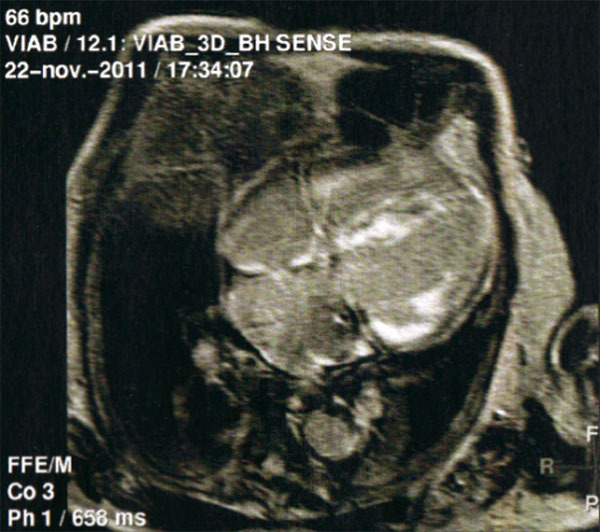

Amylose cardiaque

IRM cardiaque : aspect typique de rehaussement tardif après injection de gadolinium.